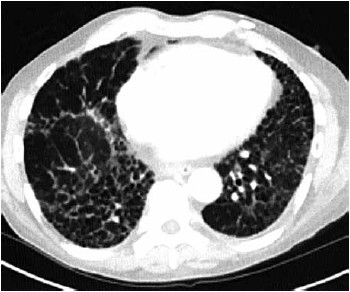

Homem de 67 anos é avaliado por dispneia gradualmente progressiva e tosse seca nos últimos 6 meses. Ele tem um histórico de tabagismo de 30 maços/ano, mas parou há 10 anos. O restante dos antecedentes mórbidos não é relevante. Exame físico: frequência respiratória: 22 ipm; saturação de oxigênio: 93% em ar ambiente; ausculta pulmonar: crepitações inspiratórias finas (tipo velcro) em ambas as bases pulmonares; nota-se baqueteamento digital. A espirometria mostra capacidade vital forçada (CVF) de 55% do previsto; relação VEF1/CVF de 0,91; DLCO de 42% do previsto. A tomografia de alta resolução do tórax é mostrada a seguir.

(Arquivo pessoal; imagem usada com autorização)

A principal hipótese diagnóstica é